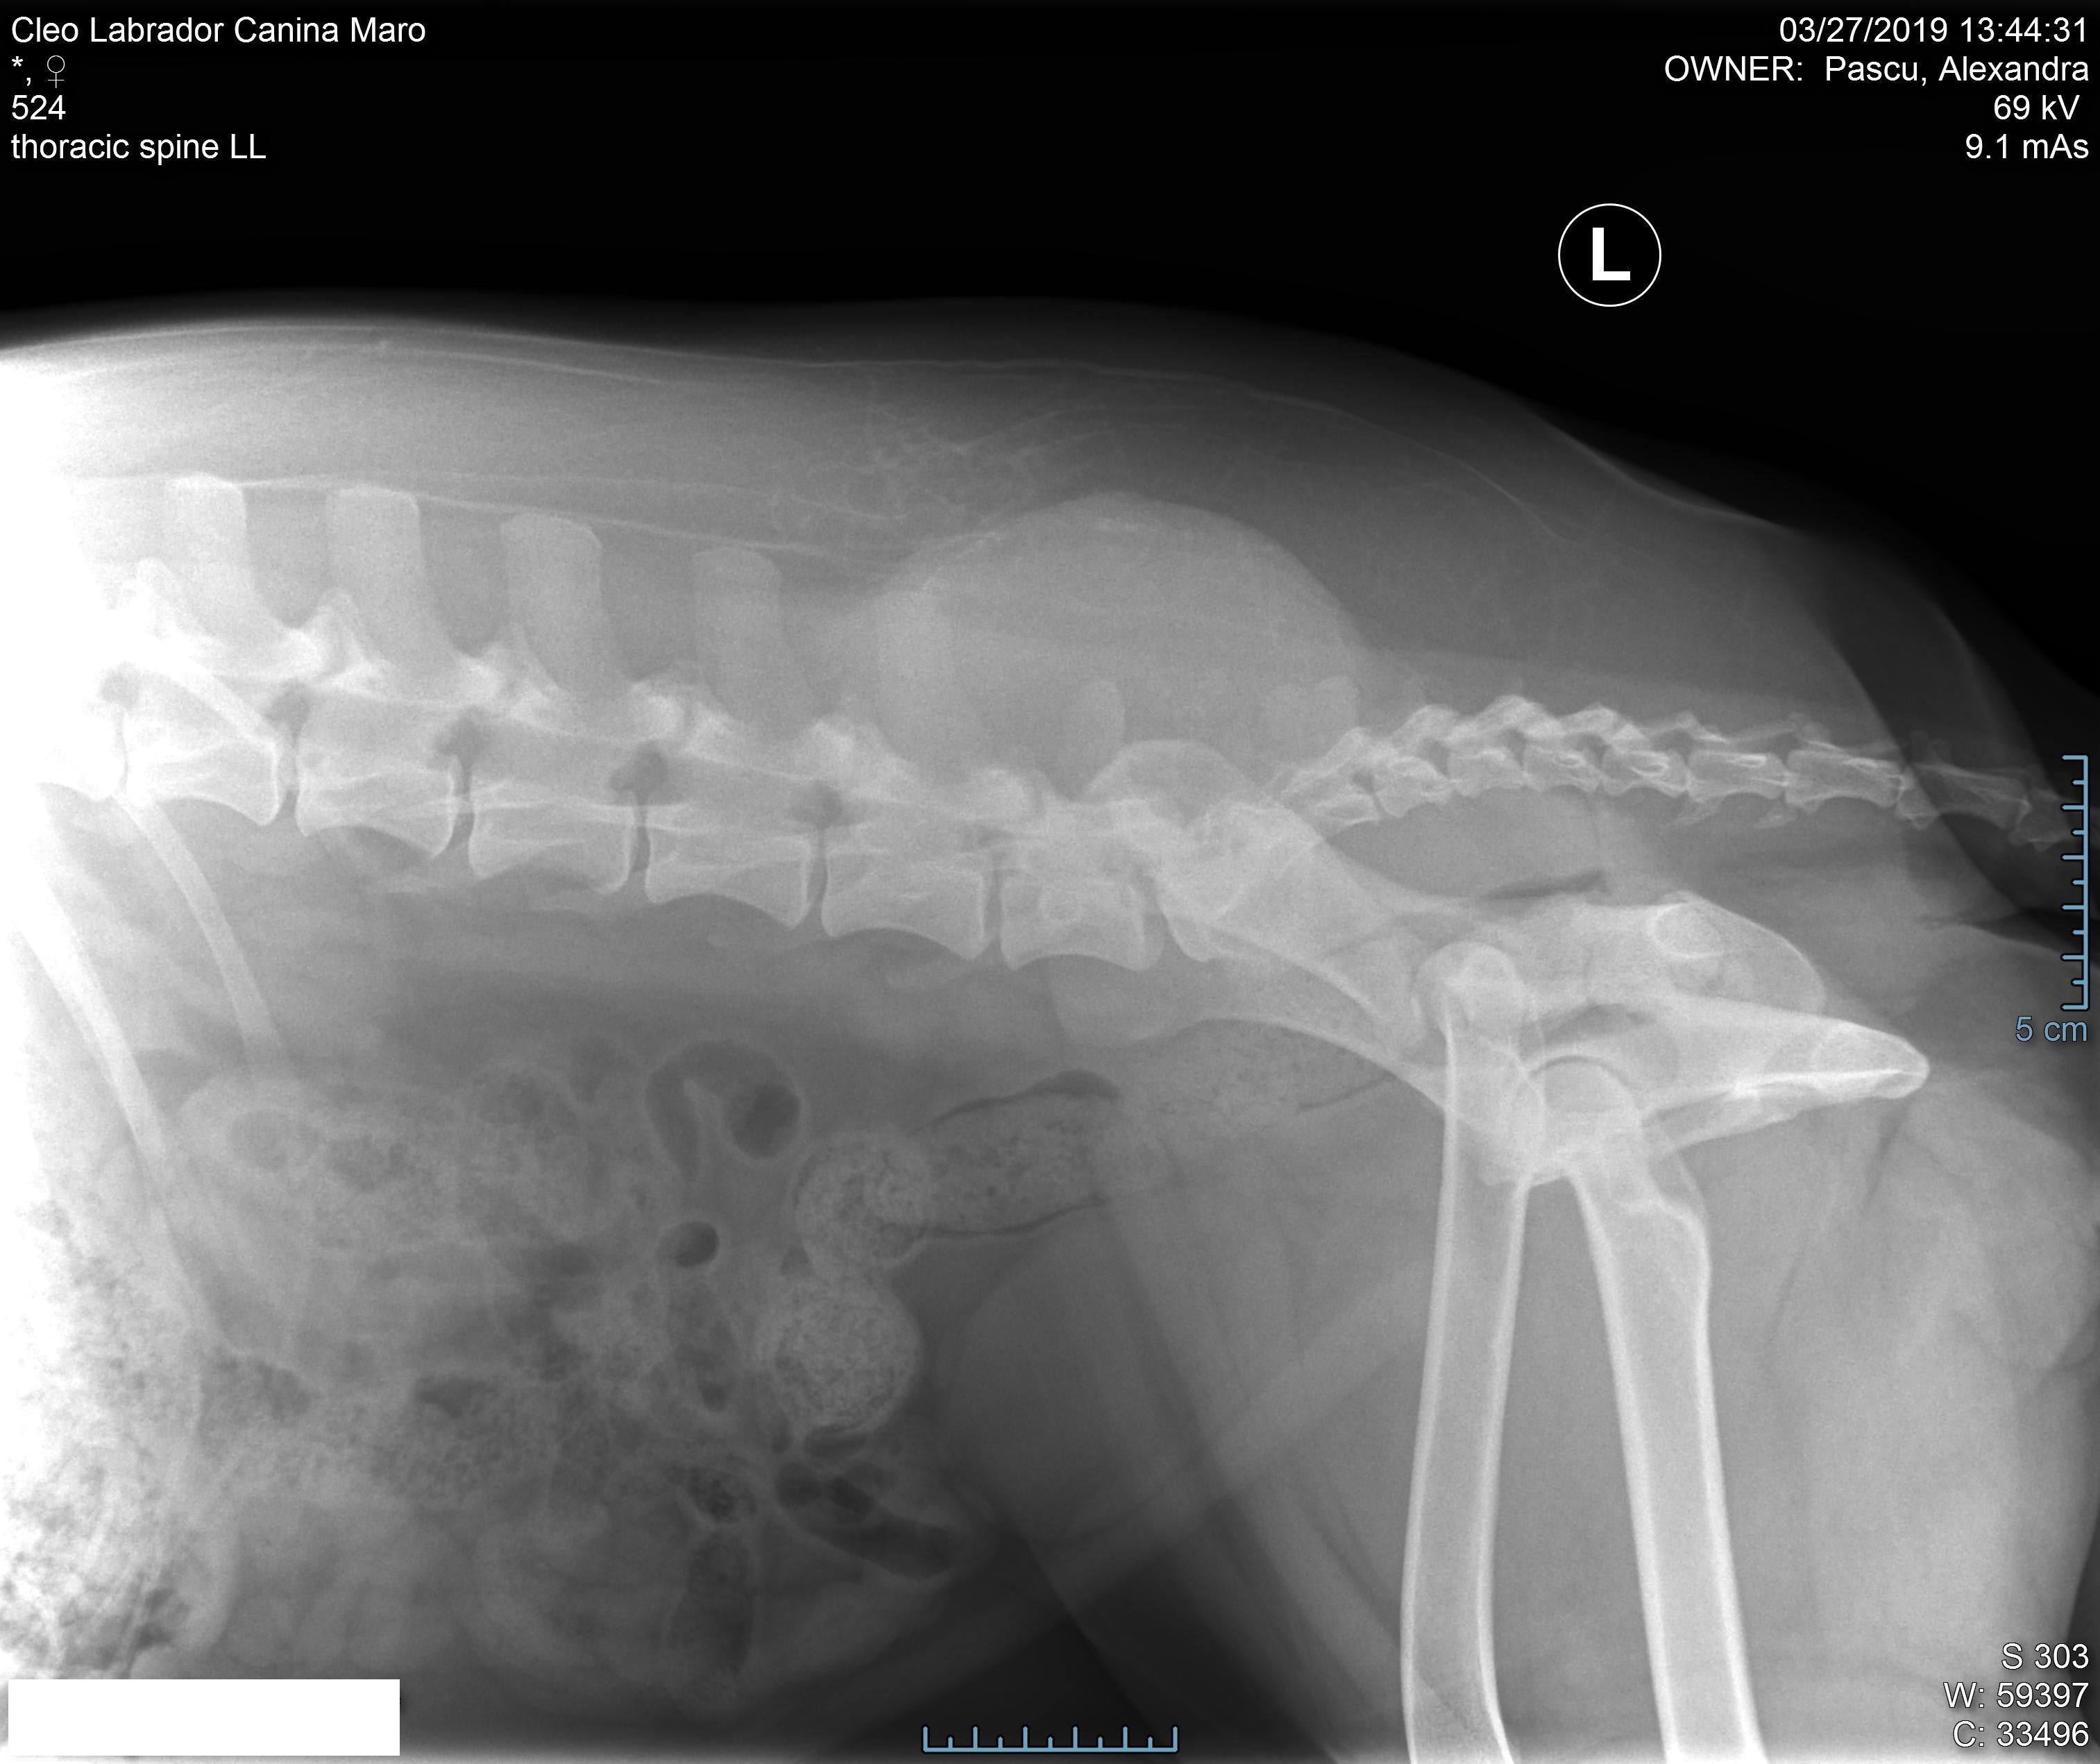

Pet's info: Dog | Labrador Retriever | Female | unspayed | 3 years and 3 months old | 36 lbs

Hi! I'm desperate to hear a second opinion about my dog case. I attached her x-Ray. The doctors said it could be something oncological as she has that injury without being Hurt. I'm about to go with her for more tests. Please help me with an advice.

Hello. That is definitely a swelling that should be further investigated. Given her age, hopefully this is something benign, but you should continue with testing to see what is going on. Hope she is well soon & thanks for using Petco Pet Education Center, formerly Petcoach.